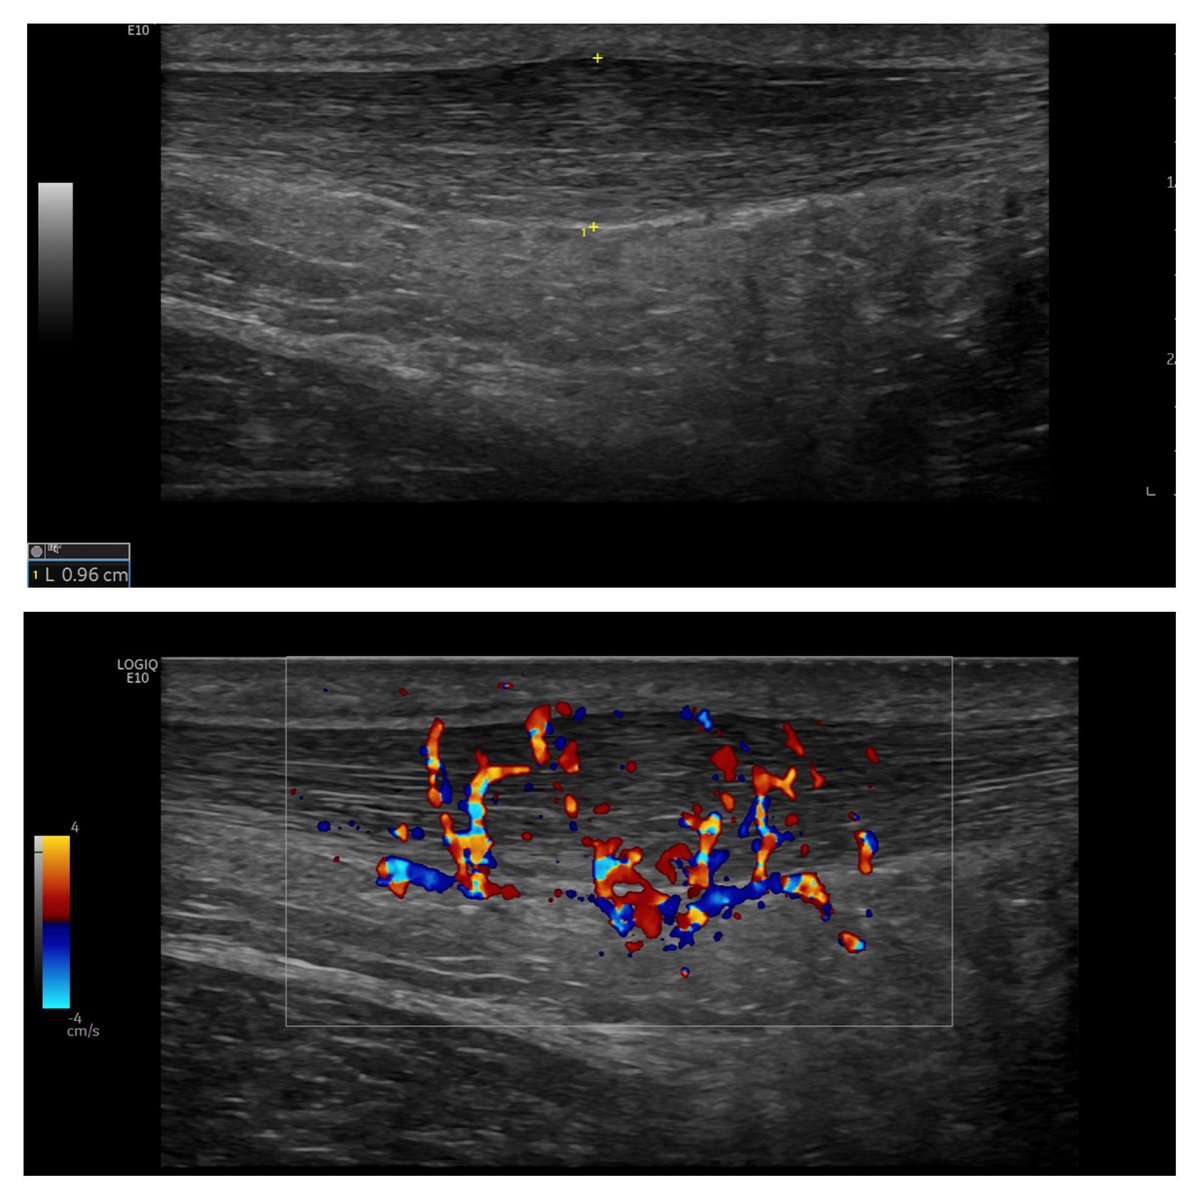

Seeing more patients OneWelbeck with painful, mid-portion Achilles tendinopathy, on a background of rapid increases in high impact load/running during lockdown. Images show thickened tendon (9.6mm diam) with florid neovascularity. GE logic E10 🏃🏽